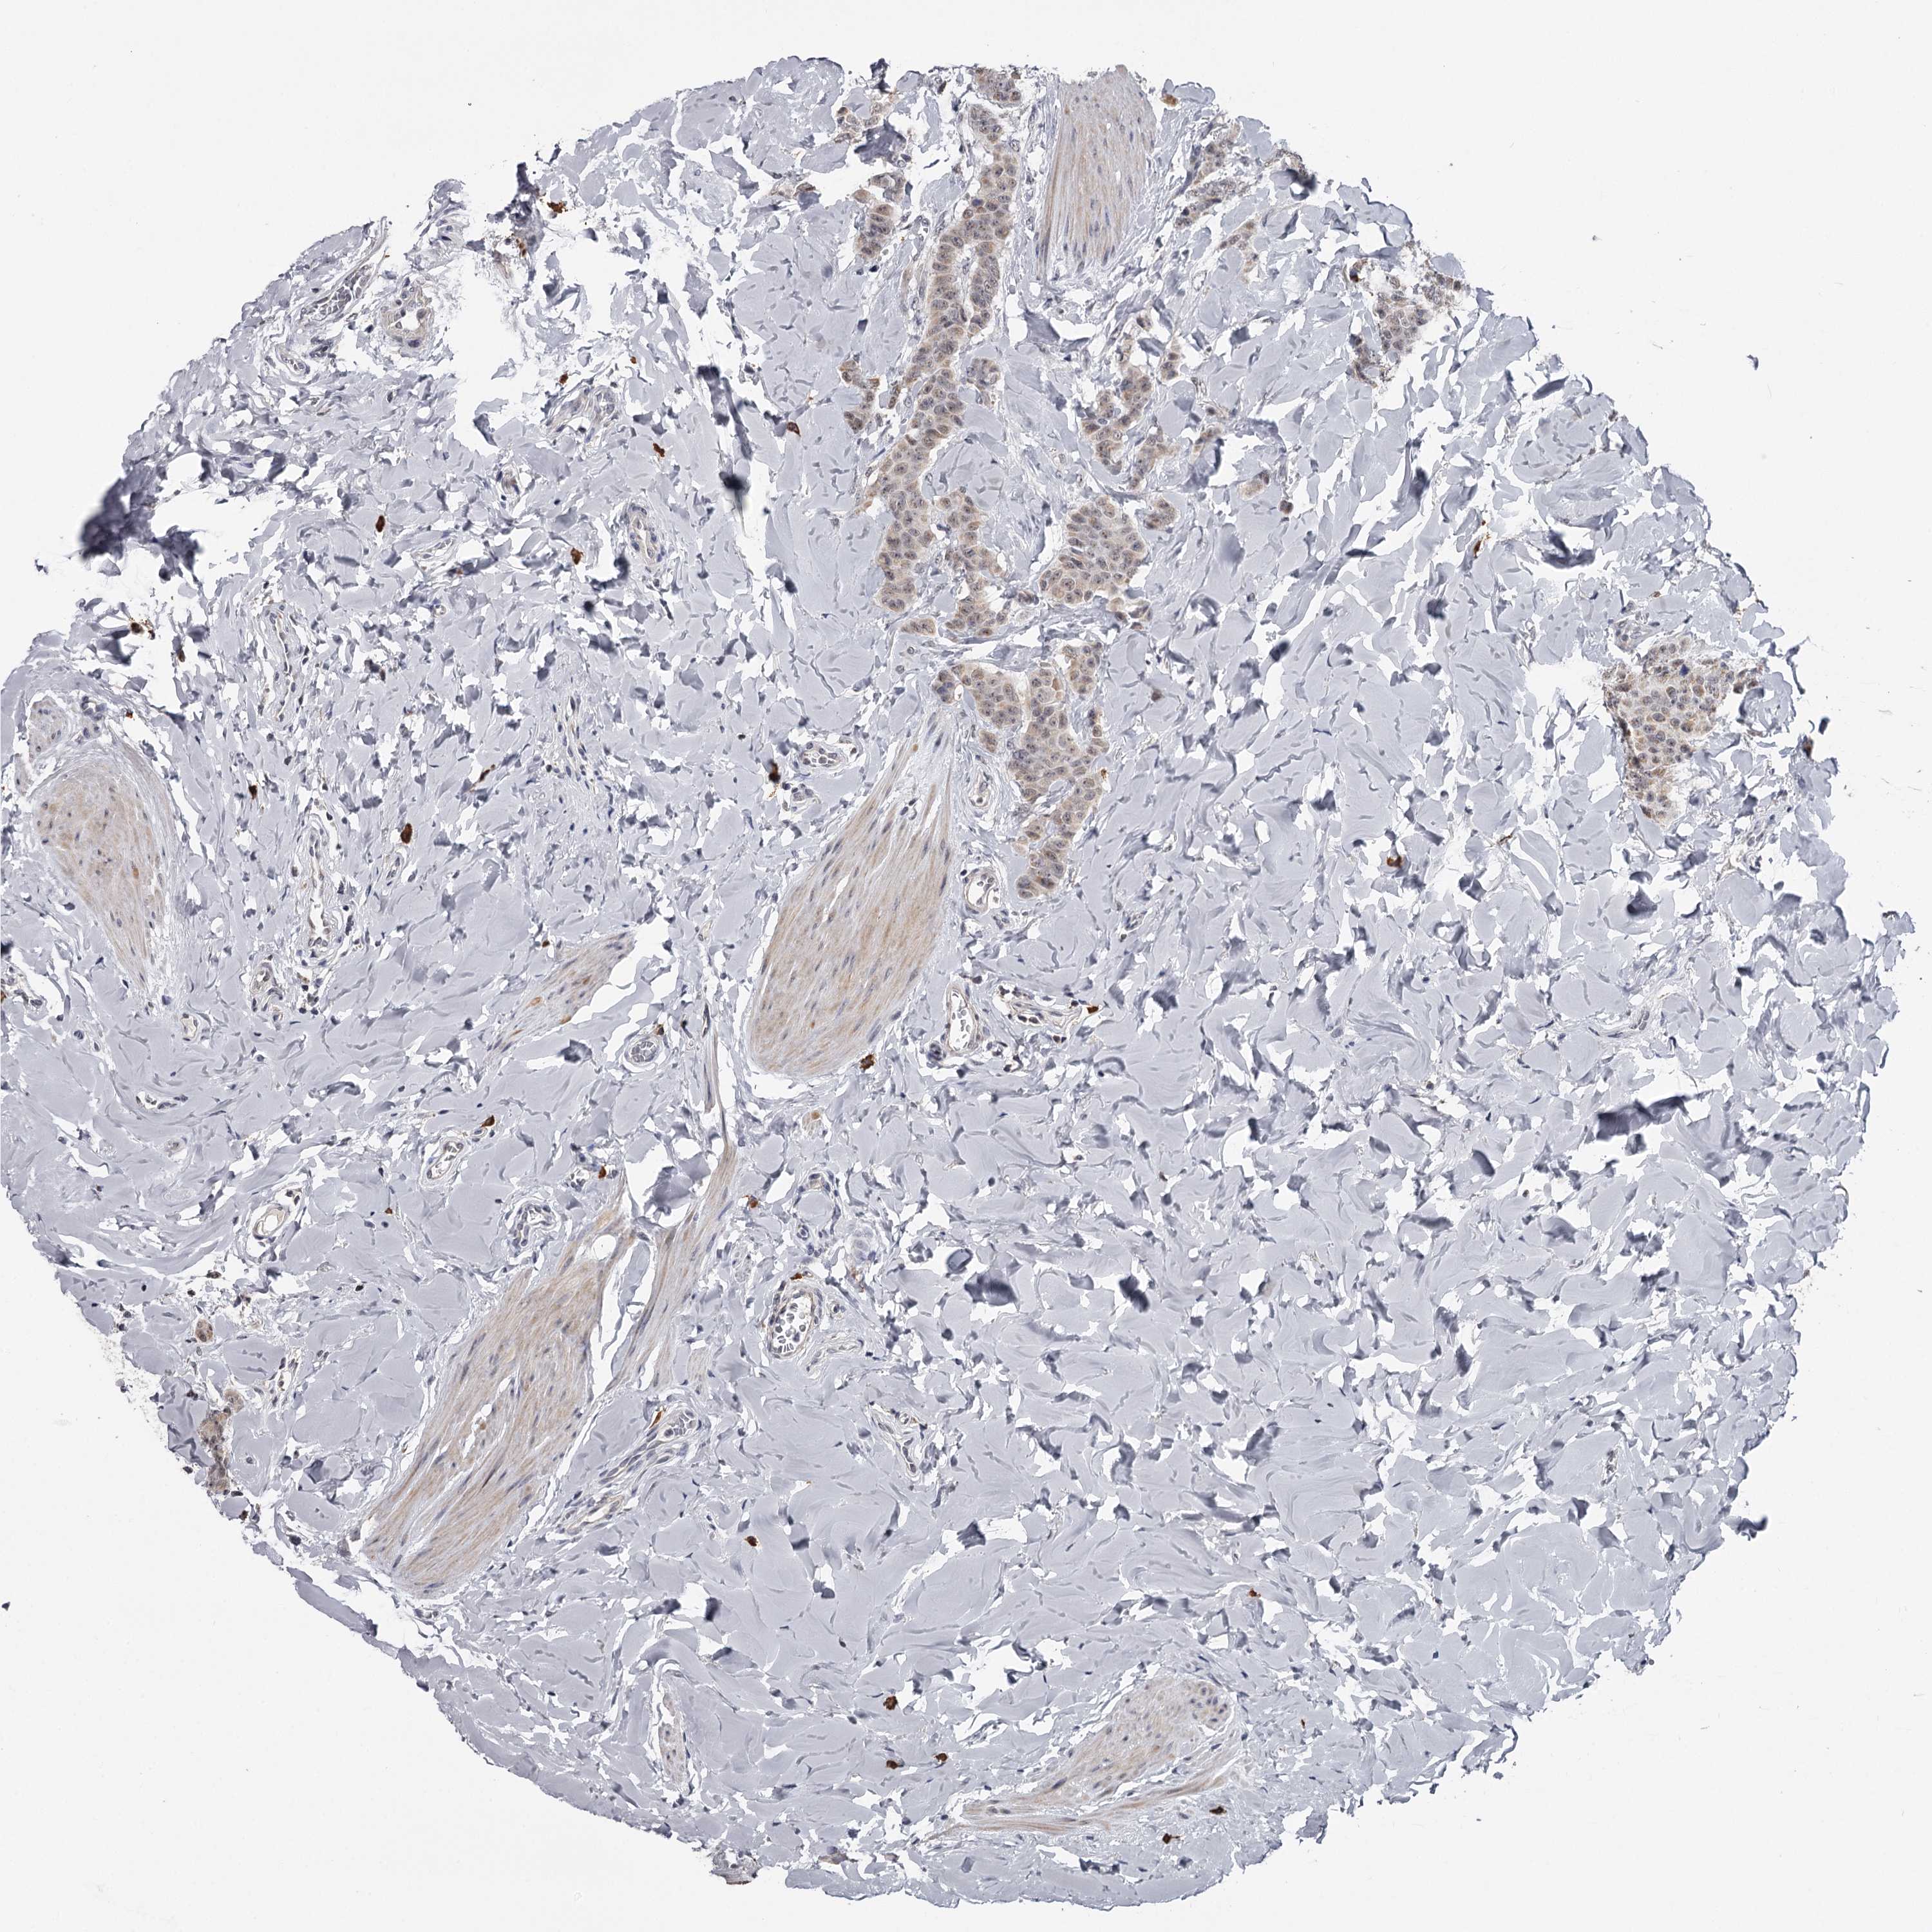

BRCA TCGA BRCA VALIDATION PROTEIN EXPRESSION